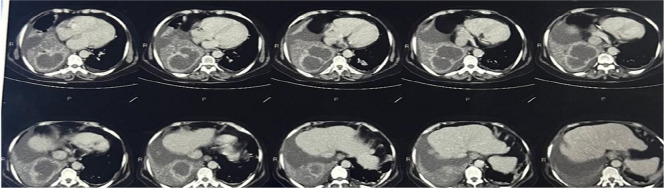

Hydatid disease can virtually involve any organs, liver being the most common followed by lungs. Pleural effusion as a complication of pulmonary hydatid cyst is exceptionally rare and its diagnosis and treatment pose significant challenges. We present an intriguing case managed in Dr D Y Patil medical college and Hospital in west India in June 2023 involving a 70-year-old female who presented with symptoms of right-sided chest pain and acute-onset dyspnoea. Referred from a local hospital, a chest radiograph revealed the presence of right pleural effusion. Subsequent radiological investigations including a contrast enhanced CT at our centre exposed two large, well-defined hypodense lesions with fluid density, encased by thick enhancing walls, along with right-sided pleural effusion and hence a diagnosis of lung abscess with right pleural effusion (right parapneumonic effusion) was established. Despite ongoing care, clinical improvement eluded us. Thoracocentesis yielded a surprising revelation - the pleural fluid was transudative with visible hooklets and protoscolices, indicating a ruptured pulmonary hydatid cyst. The patient began albendazole treatment and received a CVTS consultation. They recommended a right lower lobe lobectomy, now scheduled for the near future.